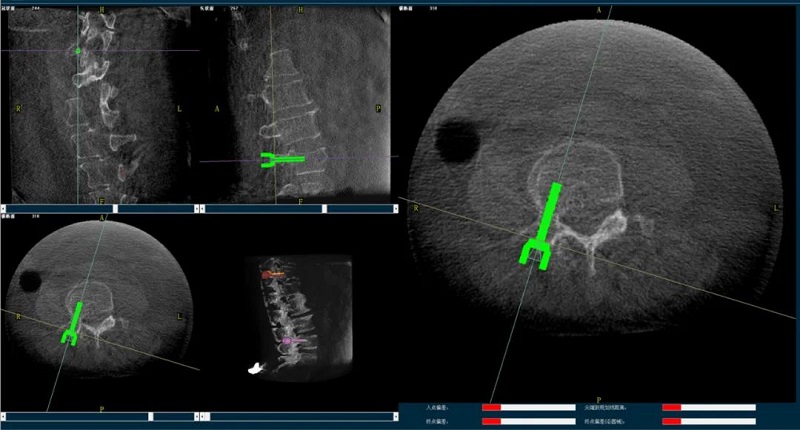

(1)首先使用普愛醫療三維C形臂采集胸腰椎病灶三維圖像,對傷椎進行三維重建;

(2)醫生制定個性化的手術方案,在機器人導航界面上進行路徑規劃;

(3)根據設定好的的位置和入針方向,植入引導針;